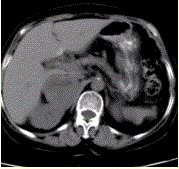

问题 患者男,41岁,发作性头晕、恶心、面色苍白伴高血压半年,入院观察,当时测血压180/80mmHg;上腹部CT示:右侧肾上腺区有直径为5cm圆形稍高密度影,边界清晰,内部密度不均(下图)。 当患者出现高血压危象时,应立即静脉缓慢推注

选项 A.酚妥拉明 B.利多卡因 C.地塞米松 D.去甲肾上腺素 E.肾上腺

答案 A